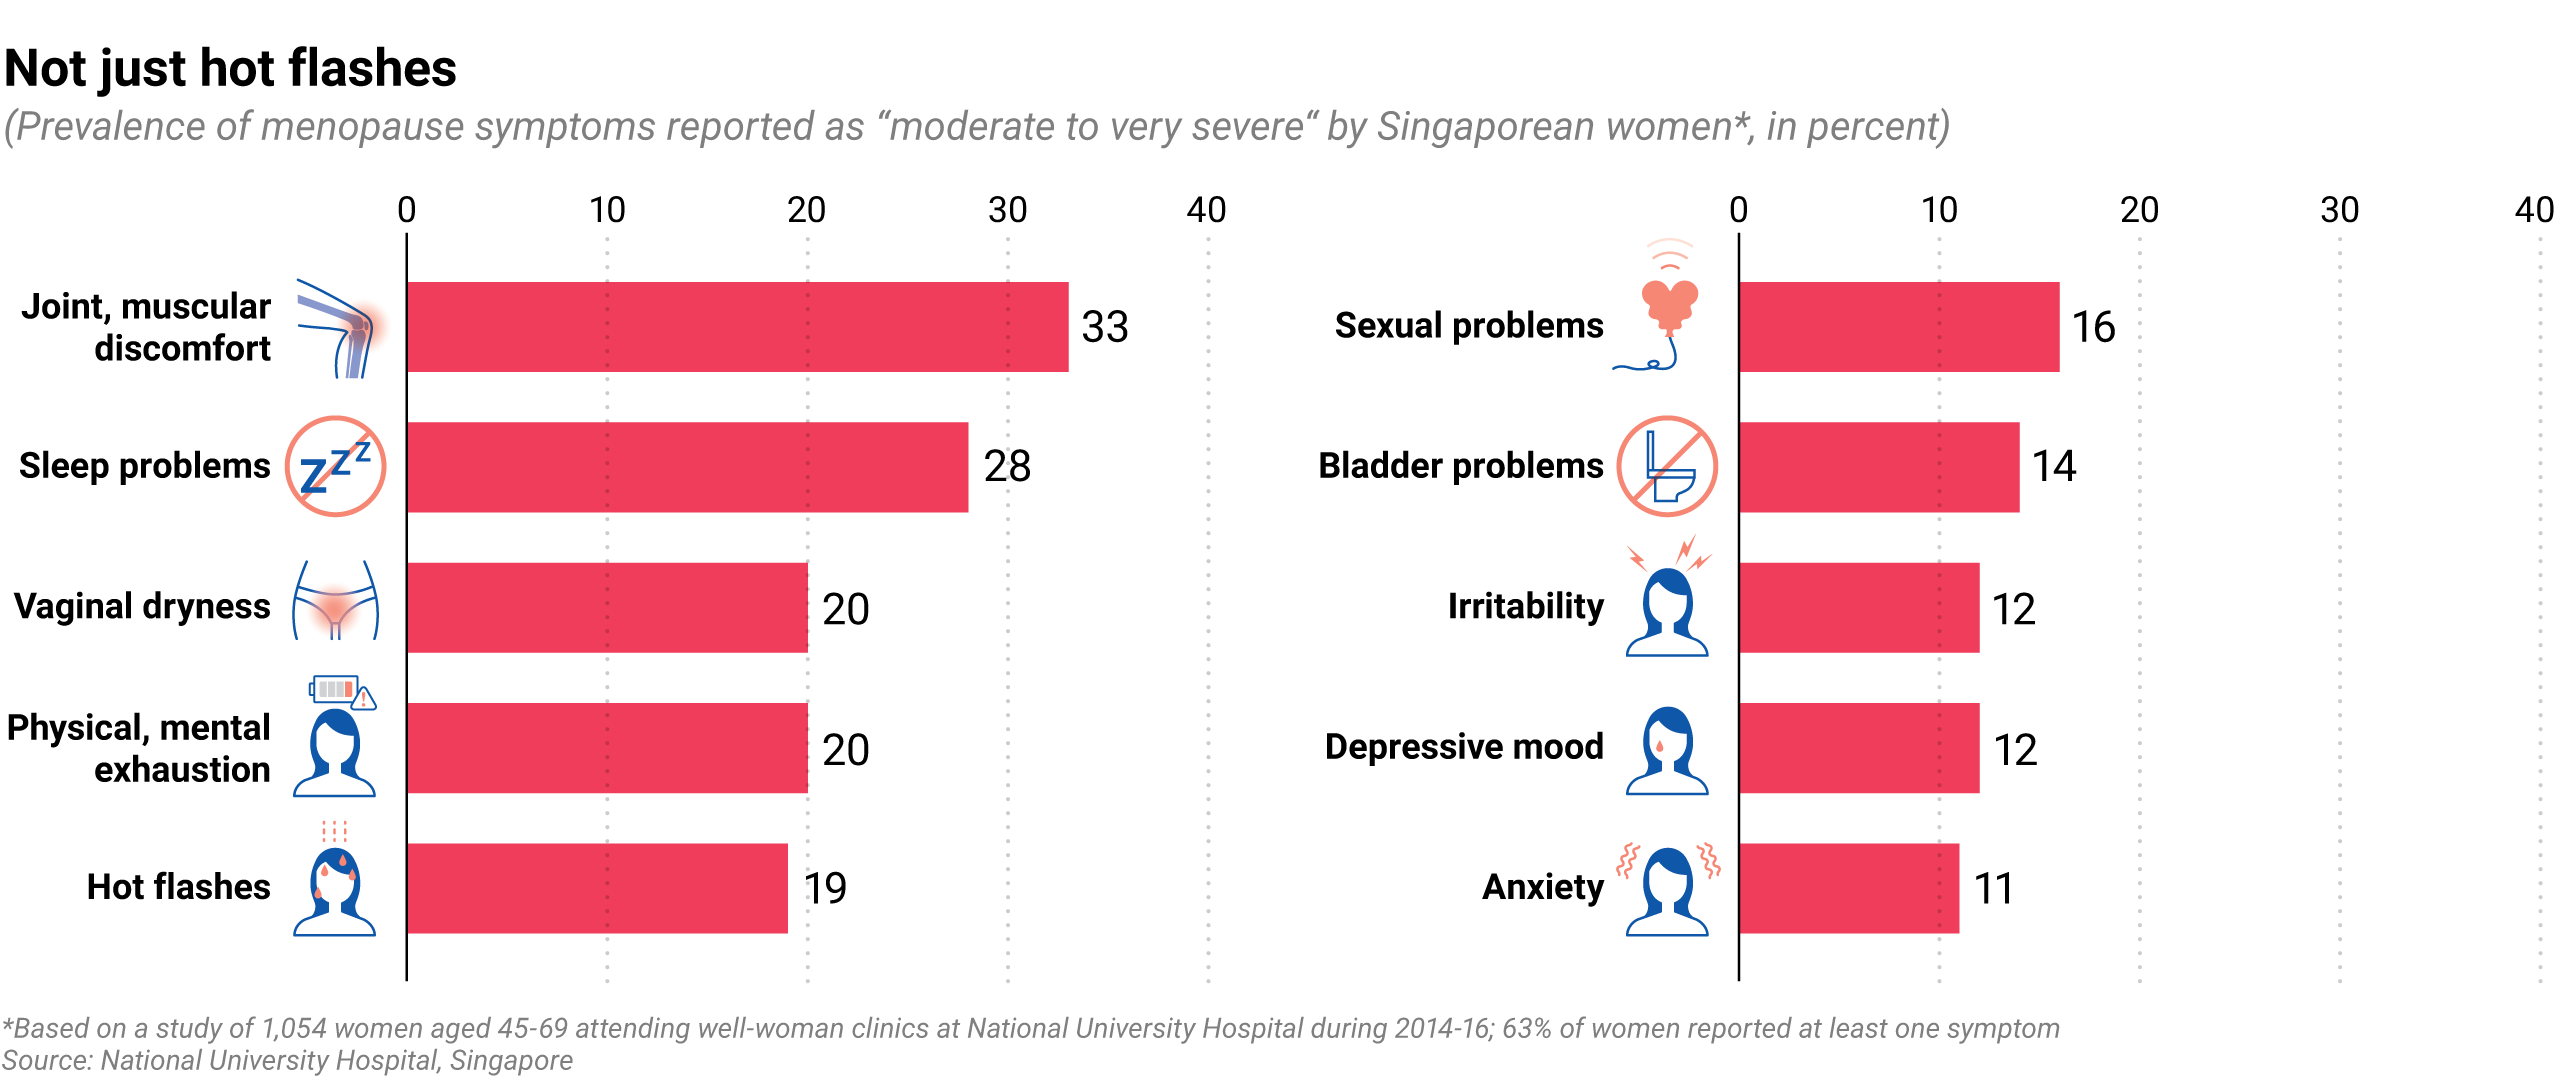

Small-scale studies so far suggest women in Asia experience menopause symptoms at similar rates to their Western counterparts but are less likely to exhibit those typically reported by women in the U.S. and Europe, like hot flashes and nausea.

According to the North American Menopause Society, around 75% of women in the U.S. experience hot flashes during their menopausal years. In contrast, data released last year by Singapore’s National University Hospital revealed the most prevalent menopause symptom amongst Singaporean women of Chinese, Malay and Indian descent was joint and muscle pain, with hot flashes detected in only 19% of the 1,000 women surveyed.

The highly personalized nature of menopause – symptoms and severity vary from woman to woman – makes large-scale data collection vital for developing new treatments, Huang added.